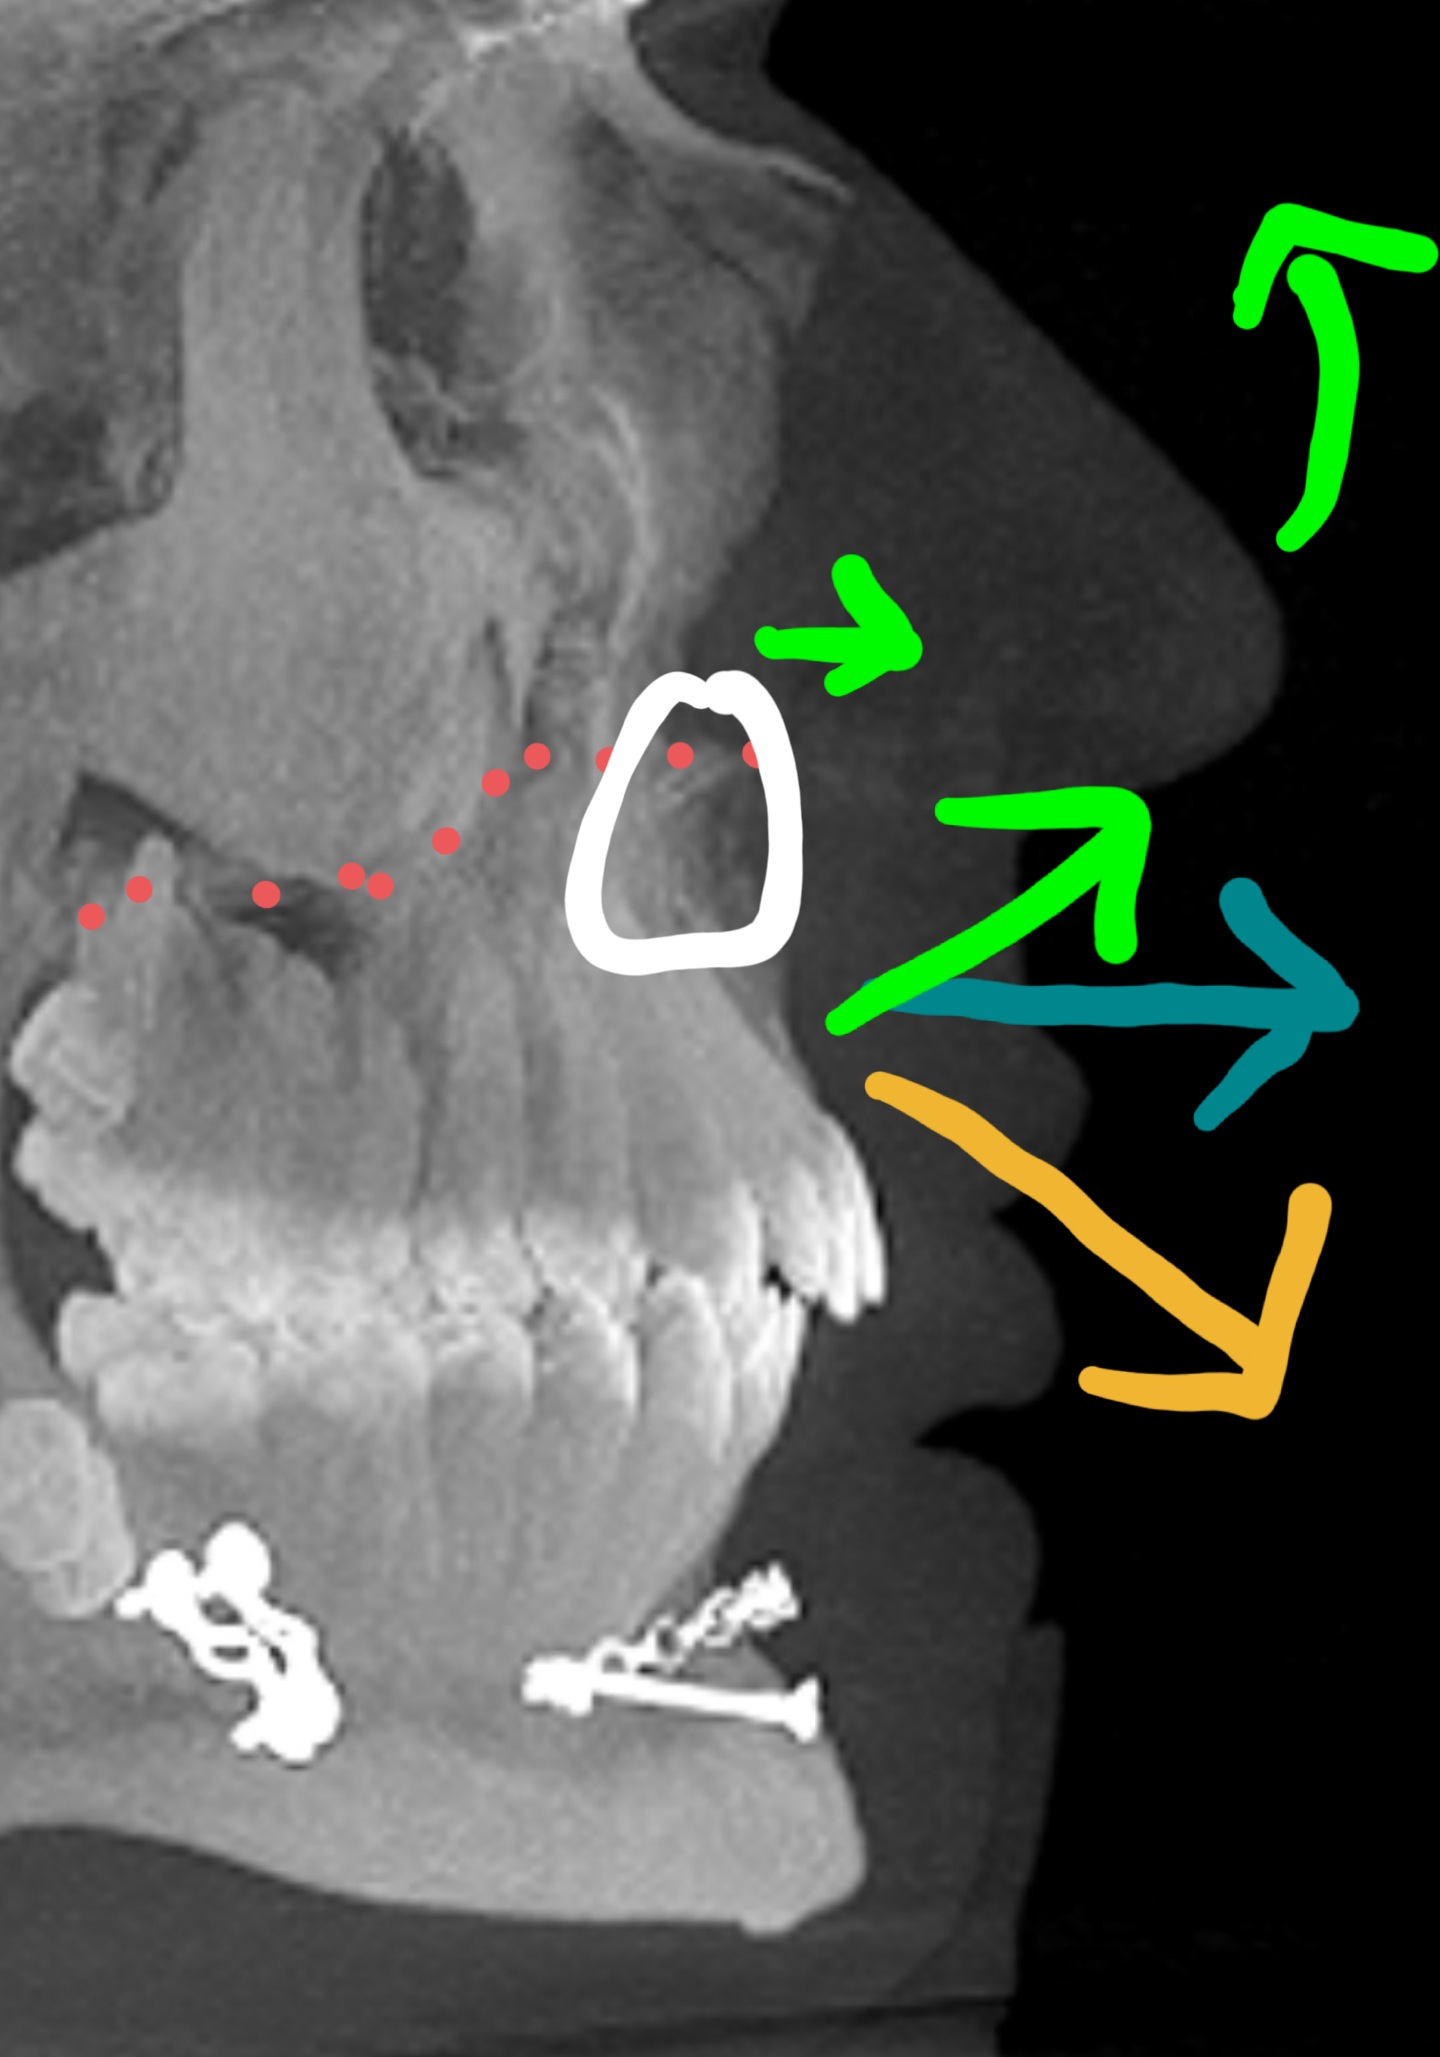

Linear advancement (with flat okklusional plane): unpredictable

CW Rotation or downgrafting (yellow arrow): Chimp Lip, little to no fullness to the nose.

CCW Rotation (green): additional fullness and upturn, IF the white circled area doesn't get impacted/shaved down. Obwegeser explained it like this.

That's my understanding.